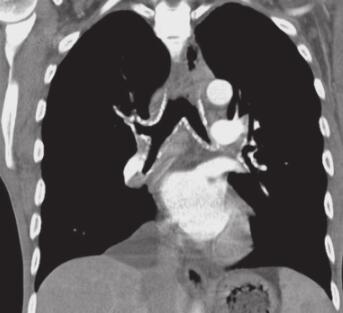

图3 肺部CT

两下肺可见片状模糊高密度影,纵隔及肺门可见多发肿大淋巴结,气管支气管软骨骨化